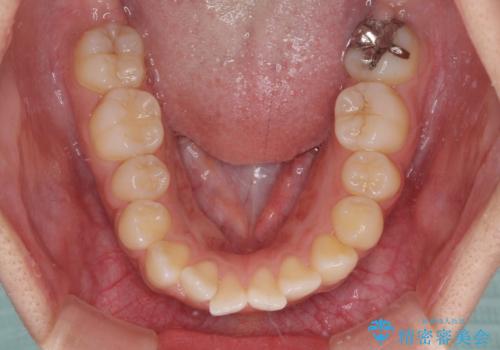

- 口元の突出感を気にして来院された患者様です。

デコボコと口元の突出感が認められたため、上下左右の第1小臼歯4本を抜歯してのワイヤー矯正を行うこととしました。

上顎歯列の横幅が狭く、下顎大臼歯の歯軸が舌側に倒れていたため、急速拡大装置により上顎骨を側方に拡大し、咬み合わせを改善することとしました。